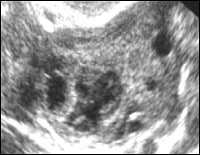

faza foliculară timpurie.

Ovarului.

În faza timpurie a proliferării sau a fazei foliculare timpurii (zilele 5-7 ale ciclului) vizualizate porțiune din unitatea folicular sunt, în principal 5-10 foliculi tertiare sau antral. Acestea din urmă au o incluziuni formă rotunjită ehonegativnoe cu diametrul de 2-6 mm, localizate în principal perimetral ovar (Fig. 9). nave spirală de rețea din jurul foliculului în curs de dezvoltare are loc in faza antrală timpurie. Astfel, fluxul sanguin este vizualizat ca câteva loci culoare în stroma și la periferia foliculi antral (Fig. 10).